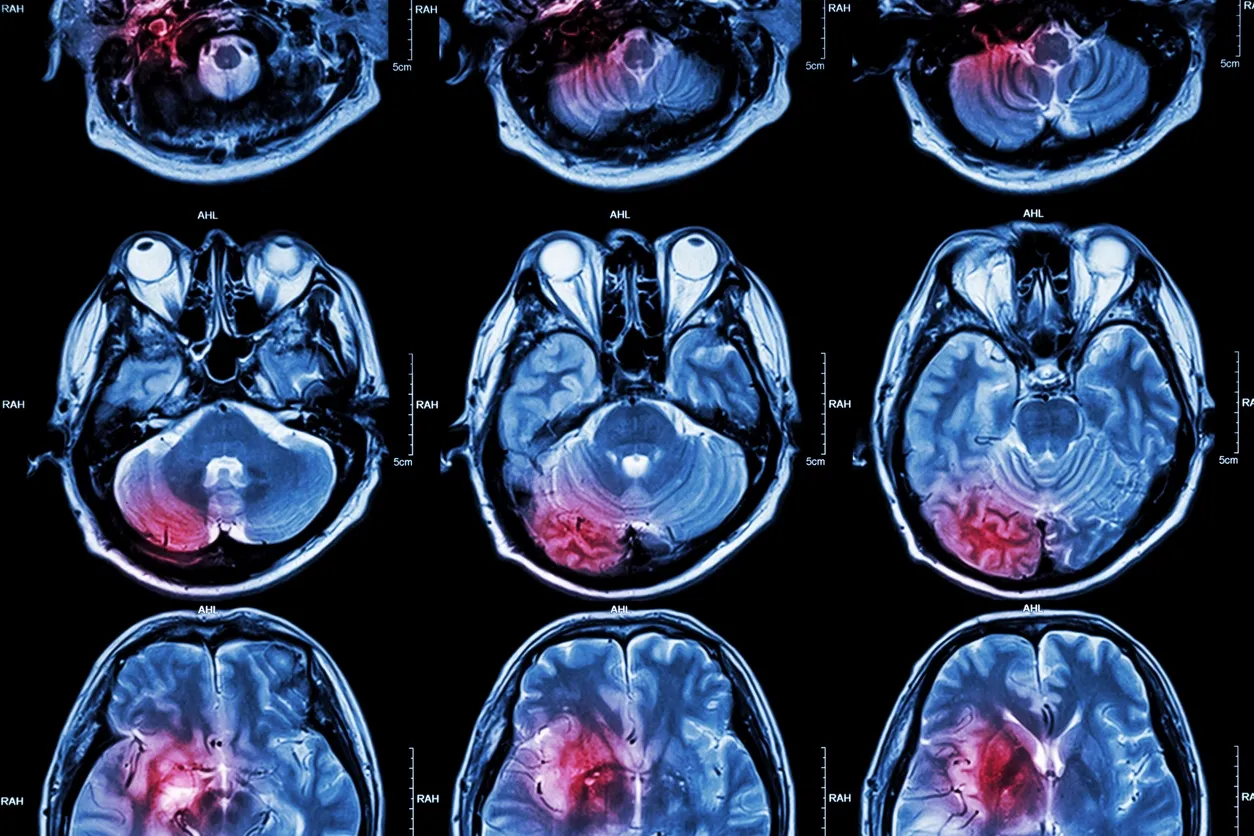

Cerebral Palsy is a group of disorders that primarily affect movement, muscle tone and coordination. This condition may also include seizures, learning disabilities, vision and dental problems, arthritis and other issues. Cerebral Palsy is primarily caused by a traumatic injury to the brain while in utero or shortly after birth. The severity and symptoms of CP vary depending on how much damage and where in the brain the injury occurred.